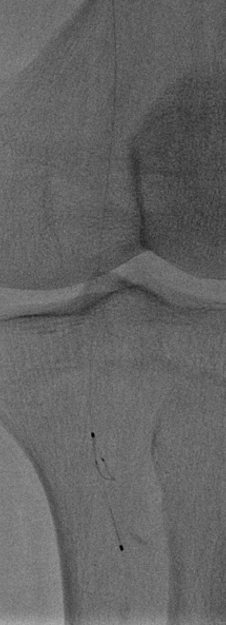

图为:评估血管准备:闭塞段残余狭窄90% ELUVIA全覆盖该区域病变

图为:股腘动脉DAART+区域性DES 最终造影